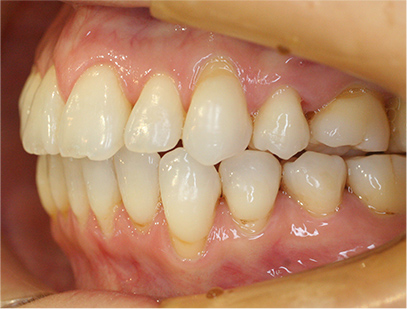

前歯にデコボコがあり、前歯が咬み合っていない症例

上下の前歯が咬んでいない事、上の前歯にデコボコがある事を主訴として来院されました。

通常通りの検査を行い「前歯部にデコボコを伴う開咬」と診断されました。

上顎は左右4番目の歯を抜歯して、下顎は横に拡大してスペースを利用して前歯を綺麗に並べ、そして前歯部にゴムを使用して咬み合わせを改善することにしました。

上下共に表側の白い矯正装置(セラミック)、マウスピース矯正

治療前の写真を比べると上下の前歯は綺麗に並び、歯が出ていたことも改善され、 上下の歯はしっかり咬み合っています。 治療期間は、重度の開咬であったために3年弱を必要としました。

• 歯並びが綺麗になり、上下の歯が咬み合った事。

• 上の前歯が出ていたことが改善された事。